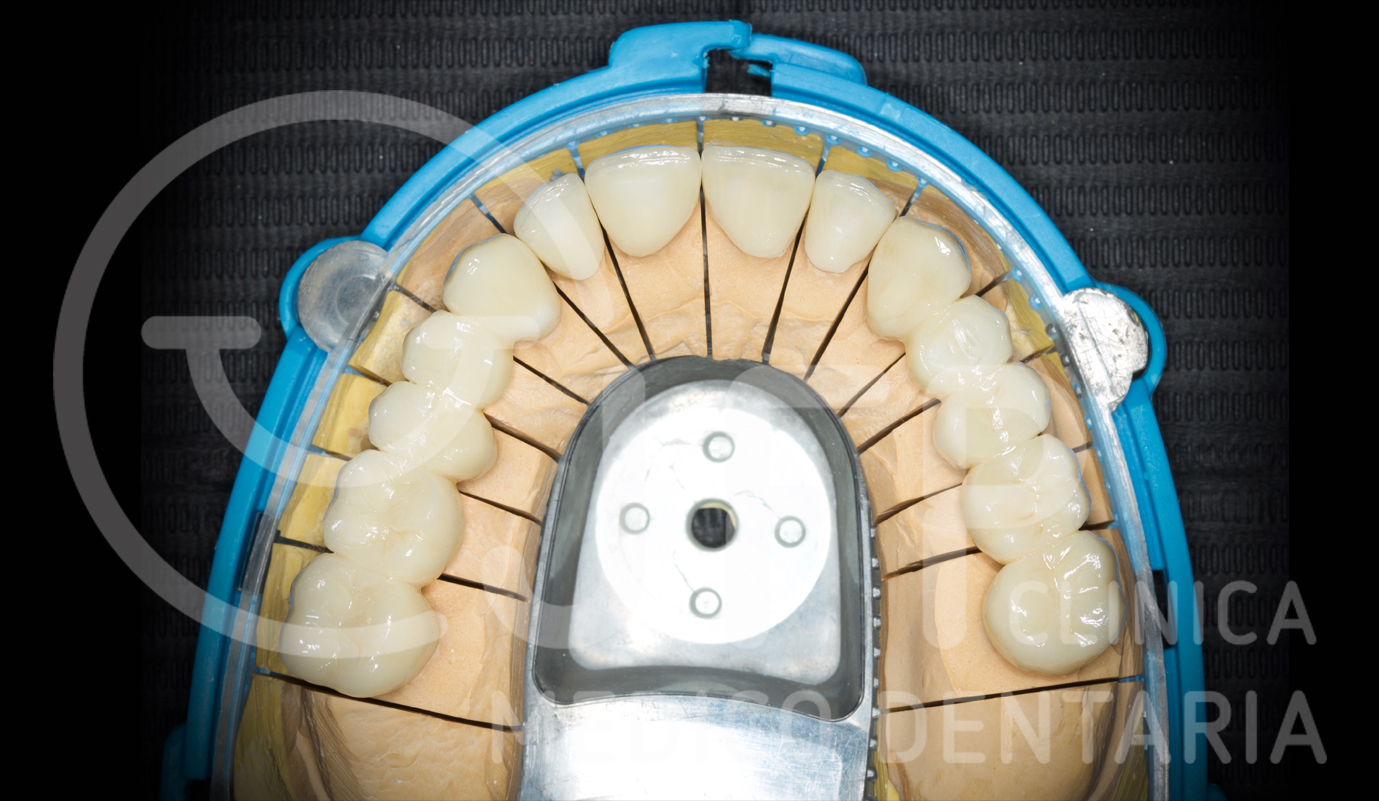

Exemplos em fase laboratorial

Casos de próteses sobre implantes